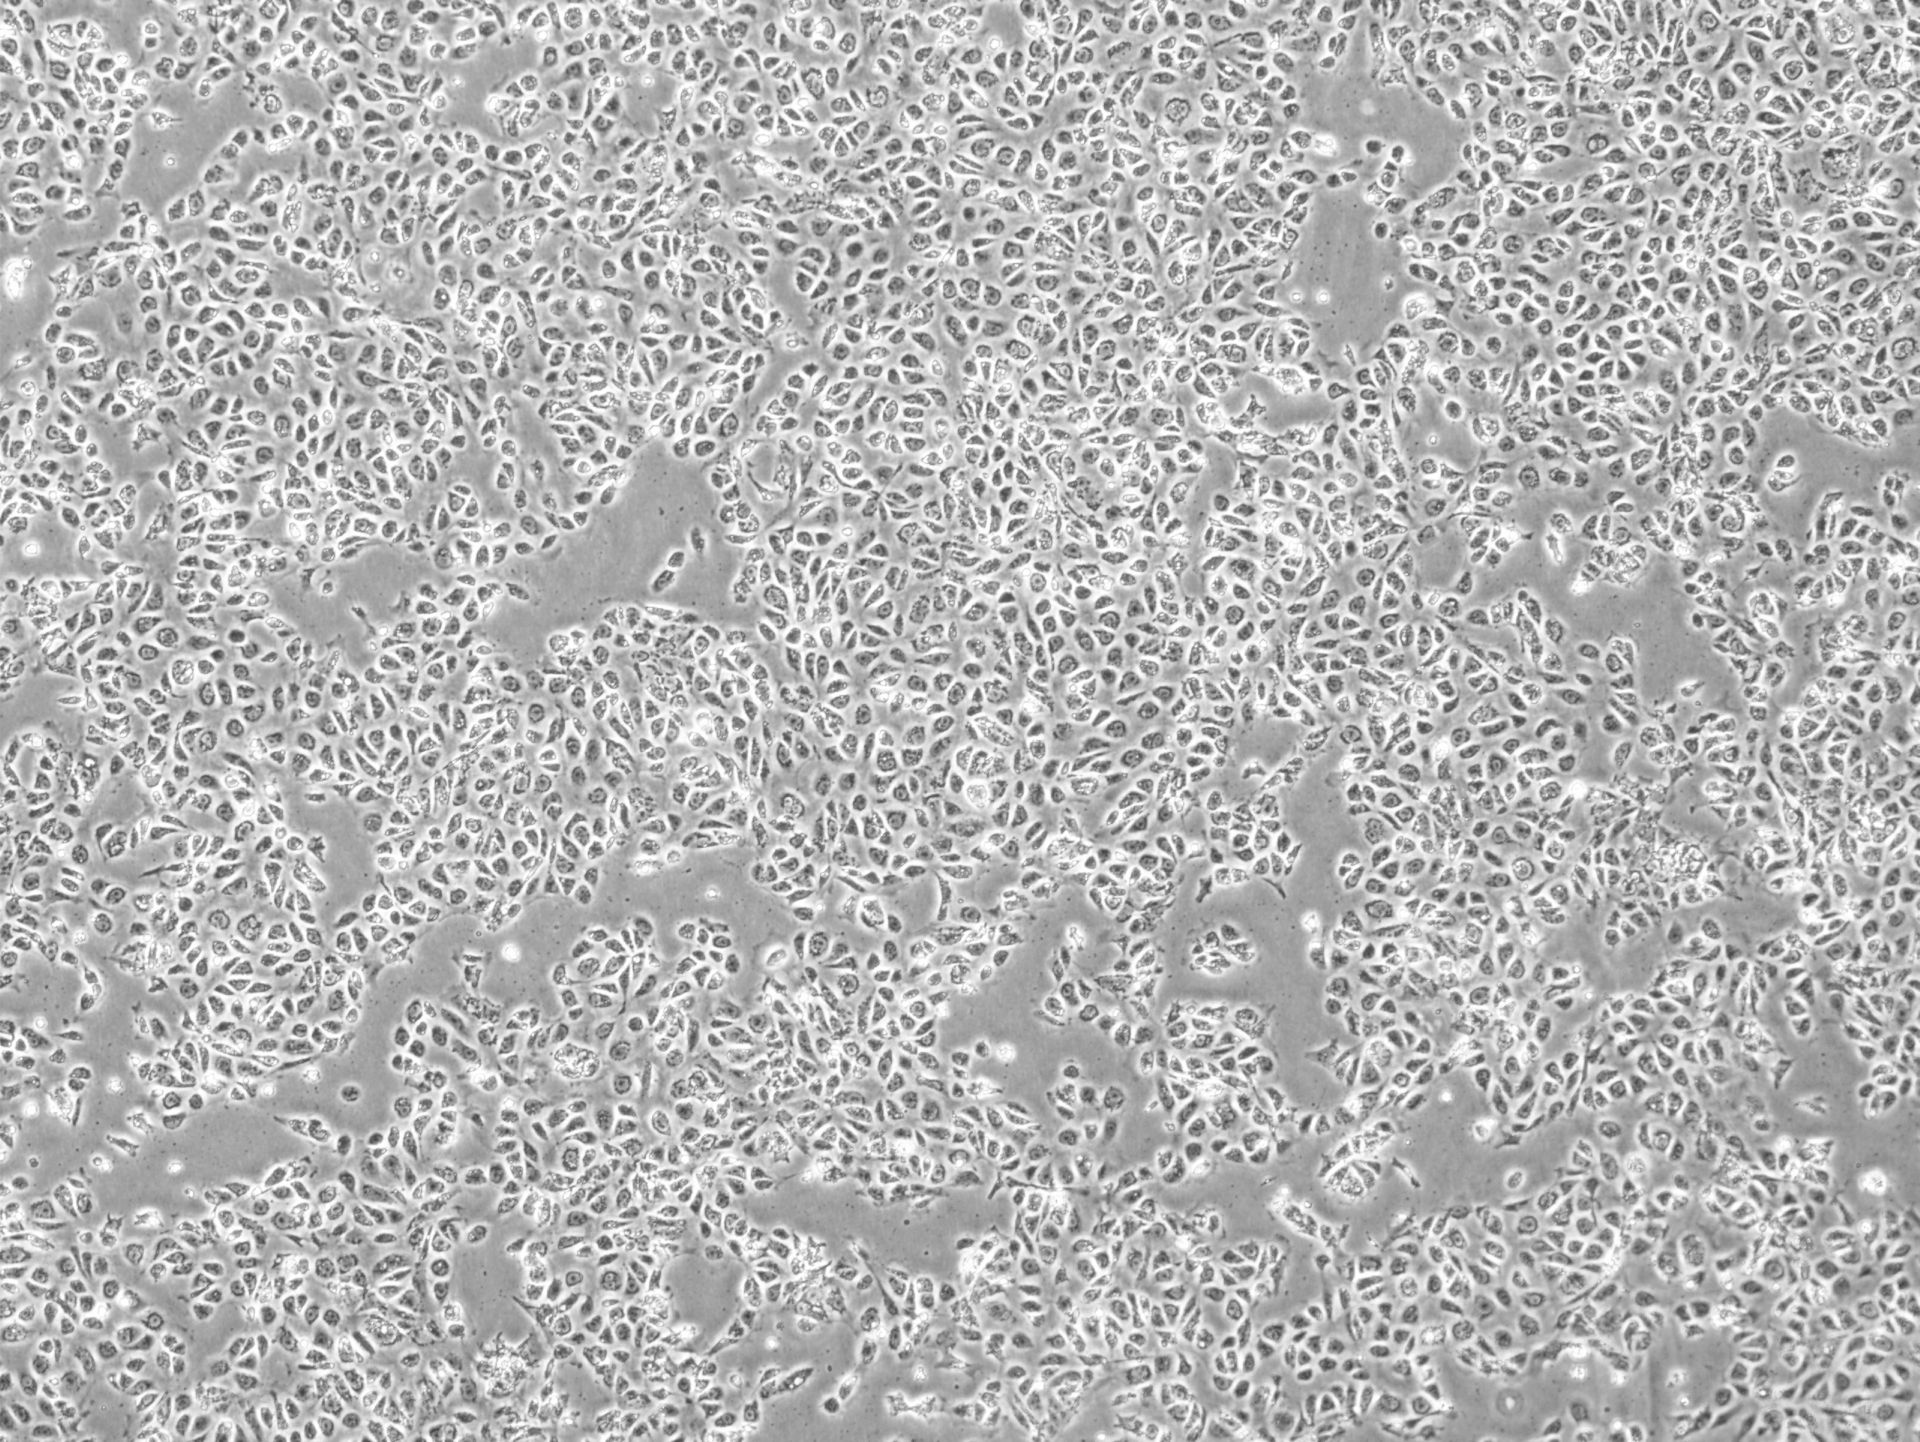

Karis Bio recently launched a first-in-human study in South Korea using an autologous therapy derived from induced pluripotent stem cells (iPSCs). The company said this represents a significant advancement in regenerative medicine and could shape the future of personalized treatment approaches.

The use of autologous iPSC-derived therapies remains a promising but complex area of regenerative medicine, due to challenges in standardization, cost, and logistics. However, both companies believe their technologies can overcome these limitations through integration of automation and biologically relevant innovations.